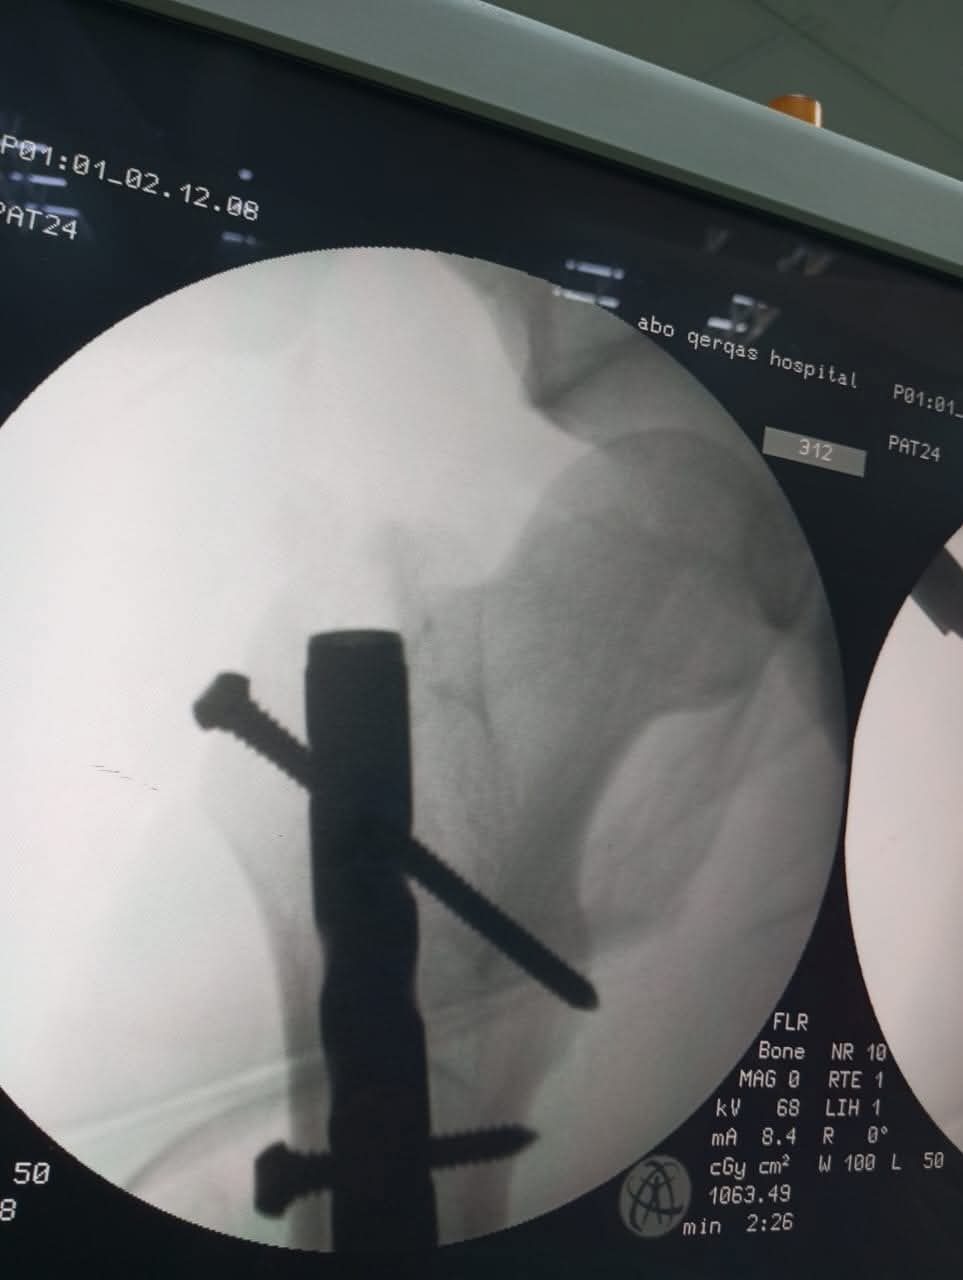

قرر الفريق الطبي استخدام تقنية المسمار النخاعي التشابكي (Interlocking Nail)، وهي من أحدث الطرق العالمية في علاج كسور العظام الطويلة، حيث توفر استقراراً فورياً للكسر، وتسمح للمريض بالبدء في التماثل للشفاء والحركة في وقت قصير جداً مقارنة بالطرق التقليدية.

فريق الجراحة: د. أحمد علاء (أخصائي العظام).

فريق الأشعة: أ. رفعت (فني الأشعة)